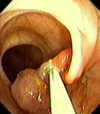

What is the most common type of neoplastic polyp?

- Adenomatous

- Image of pedunculated attached here